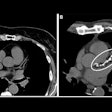

CT image (left) of gastric cancer patient with peritoneal metastasis, along with output of deep-learning model (center and right). Images courtesy of the Shenzhen Institutes of Advanced Technology.The researchers acknowledged a number of limitations to their study, including its focus on patients in Asian populations. As a result, their algorithm needs to be further evaluated in other ethnic groups, according to the authors.